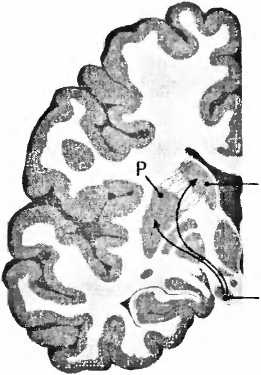

Для болезни Паркинсона характерно отмирание дофаминовых клеток в черной субстанции (substantia nigra) мозгового ствола (рис. 23). При вскрытии эта область мозга из-за пигментации клеток, вырабатывающих дофамин, выглядит как проходящая через мозговую ткань черная лента. И если эти клетки мертвы, их сразу же видно, как, например, при болезни Паркинсона. Тогда клетки не могут больше иннервировать полосатое тело (стриатум), моторную область в центре мозга, то есть снабжать ее нервными волокнами и управлять ею. Из-за недостатка в стриатуме дофамина возникают типичные для этой болезни расстройства движения. Что может быть логичнее, чем лечить эту болезнь заменой умерших клеток? В1987 году в ведущем профессиональном журнале The New England Journal of Medicine[89] появилась статья мексиканского врача Мадрасо, в которой он сообщал о поразительном улучшении у больного паркинсонизмом после аутотрансплантации ткани дофаминсодержащих клеток надпочечников в хвостатое ядро (nucleus caudatus, рис. 23). В ближайшие два года сообщение привело к лавине из 200 подобных трансплантаций. Но операция оказалась неэффективной, и в течение двух лет после нее 20 % пациентов умерли. Исследование мозга умерших показало, что трансплантированная из надпочечников ткань в мозге не прижилась. В стриатуме были видны только шрамы. Многообещающие результаты Мадрасо были основаны, вероятно, на непрофессионально проведенных исследованиях в сочетании с эффектом плацебо (см. XVII.4).

NCSN норма

болезнь Паркинсона

Рис. 23. При болезни Паркинсона пигментированные черным клетки, производящие дофамин в черной субстанции (SN), умирают и уже больше не могут управлять моторной областью — полосатым телом стриатумом (Р — putamen, скорлупа; NC — nucleus caudatus, хвостатое ядро).